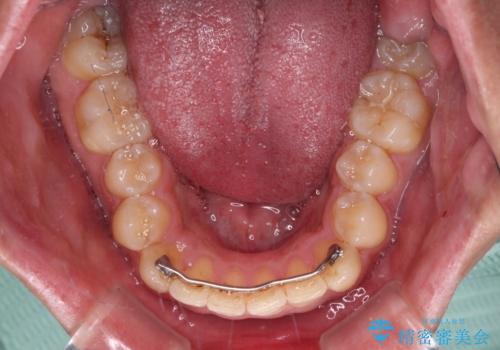

上顎歯列全体がスムーズに後方移動でき、1年で治療を終えることができました。

- 矯正治療後の保定が不十分だと後戻り(元の位置に戻ろうとする動き)をします